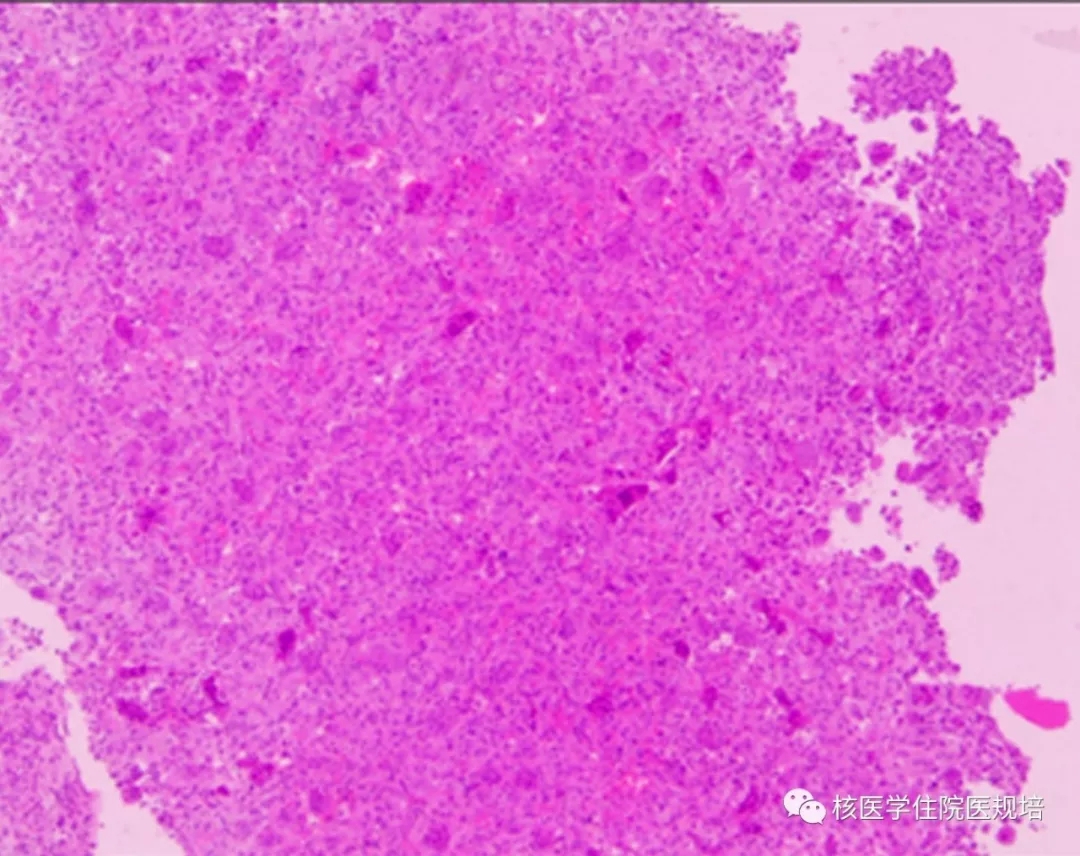

4.巨细胞瘤的病理图像

随后行肿瘤全切手术,病理诊断:骨的巨细胞瘤。